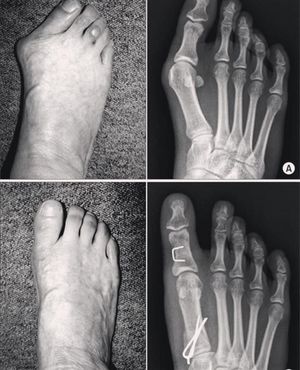

Shown here is a condition called hallux valgus before and after management.Hallux Valgus is a deformity seen in the first metatarsal as it gets deviated medially with lateral rotation of the hallux. It is of higher incidence in females than males of a ratio of 2:1 to 4:1. About 70% of patients with Hallux Valgus have a positive family history. Treatment can be opertaive and non-operative. Non-operative treatment mainly focuses on wearing a special shoes, while operative treatment is by surgical correction. Figure(A, and B) shows the deformity before and after the surgery.